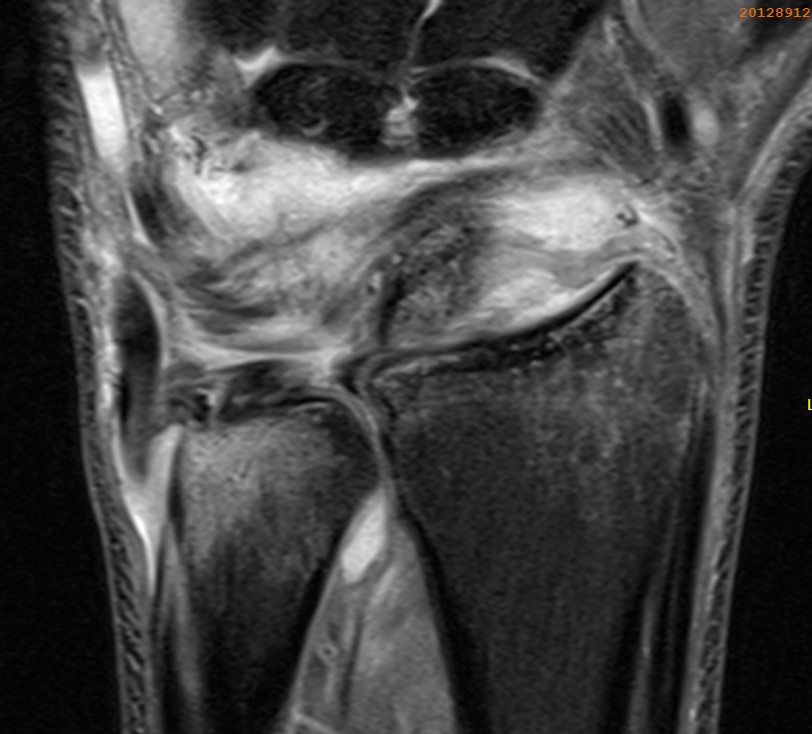

Ulno-carpal abutment

Ulnocarpal abutment and lunate chondromalacia